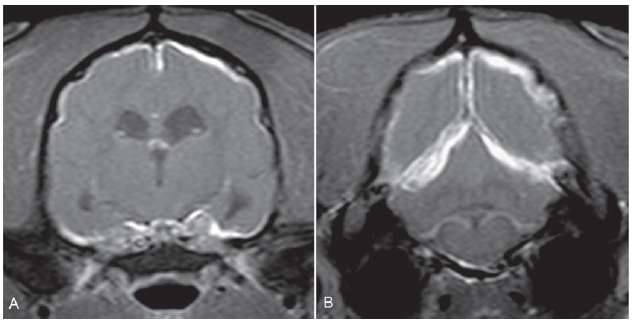

Which feline disease can cause ependymitis resulting in marked contrast enhancement of the lining of the ventricular system?

d) FIP (intracranial)